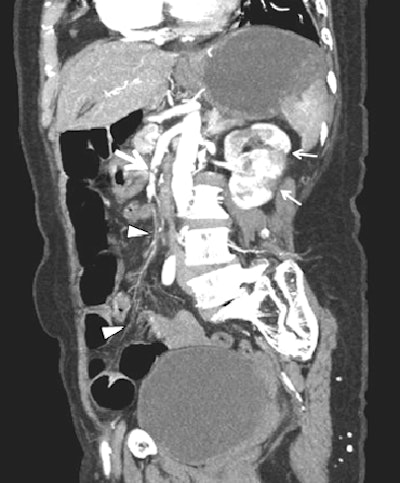

| In a 56-year-old man with acute mesenteric ischemia, neither emboli nor thrombi are definitively shown on axial arterial-phase CT (above). However, oblique coronal plane of volume-rendered image (below) shows large embolus (thick arrow) and extensive vascular occlusion (arrowheads) along the superior mesenteric artery and its branches, with multifocal renal infarction (thin arrows). Because this patient suffered from long-standing severe heart failure, mesenteric ischemia was conservatively managed with anticoagulant drugs. Images republished with permission of the American Roentgen Ray Society from AJR; 2006; 187: 1212-1221. |

MDCT also shows mesenteric emboli and focal infarction of the bowel loops; most emboli wedge at branch points in the mid to distal superior mesenteric artery, usually distal to the middle colic artery. "Meanwhile, thrombosis is most likely to occur at or near the origins of the proximal mesenteric arteries," Hong and colleagues wrote.